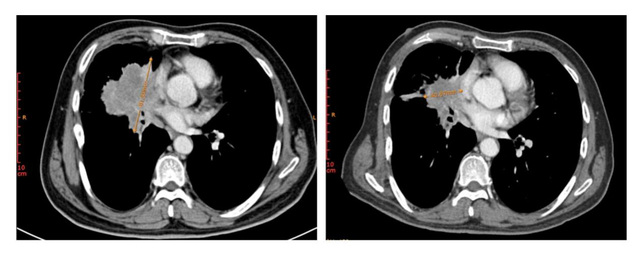

在一项评估MRG003在EGFR阳性晚期非小细胞肺癌(NSCLC)患者中的疗效和安全性的II期临床试验中,3例接受EGFR-TKI或化疗超过一年后出现疾病进展的患者接受了MRG003治疗,并且目标病灶的总直径均减少了50%以上,达到部分缓解(PR)。具体详情如下:

患者3为晚期肺鳞癌,化疗进展后接受MRG003治疗,右肺门处病灶同样在MRG003治疗后得到显著缩小,靶病灶直径总和缩小54.1%。